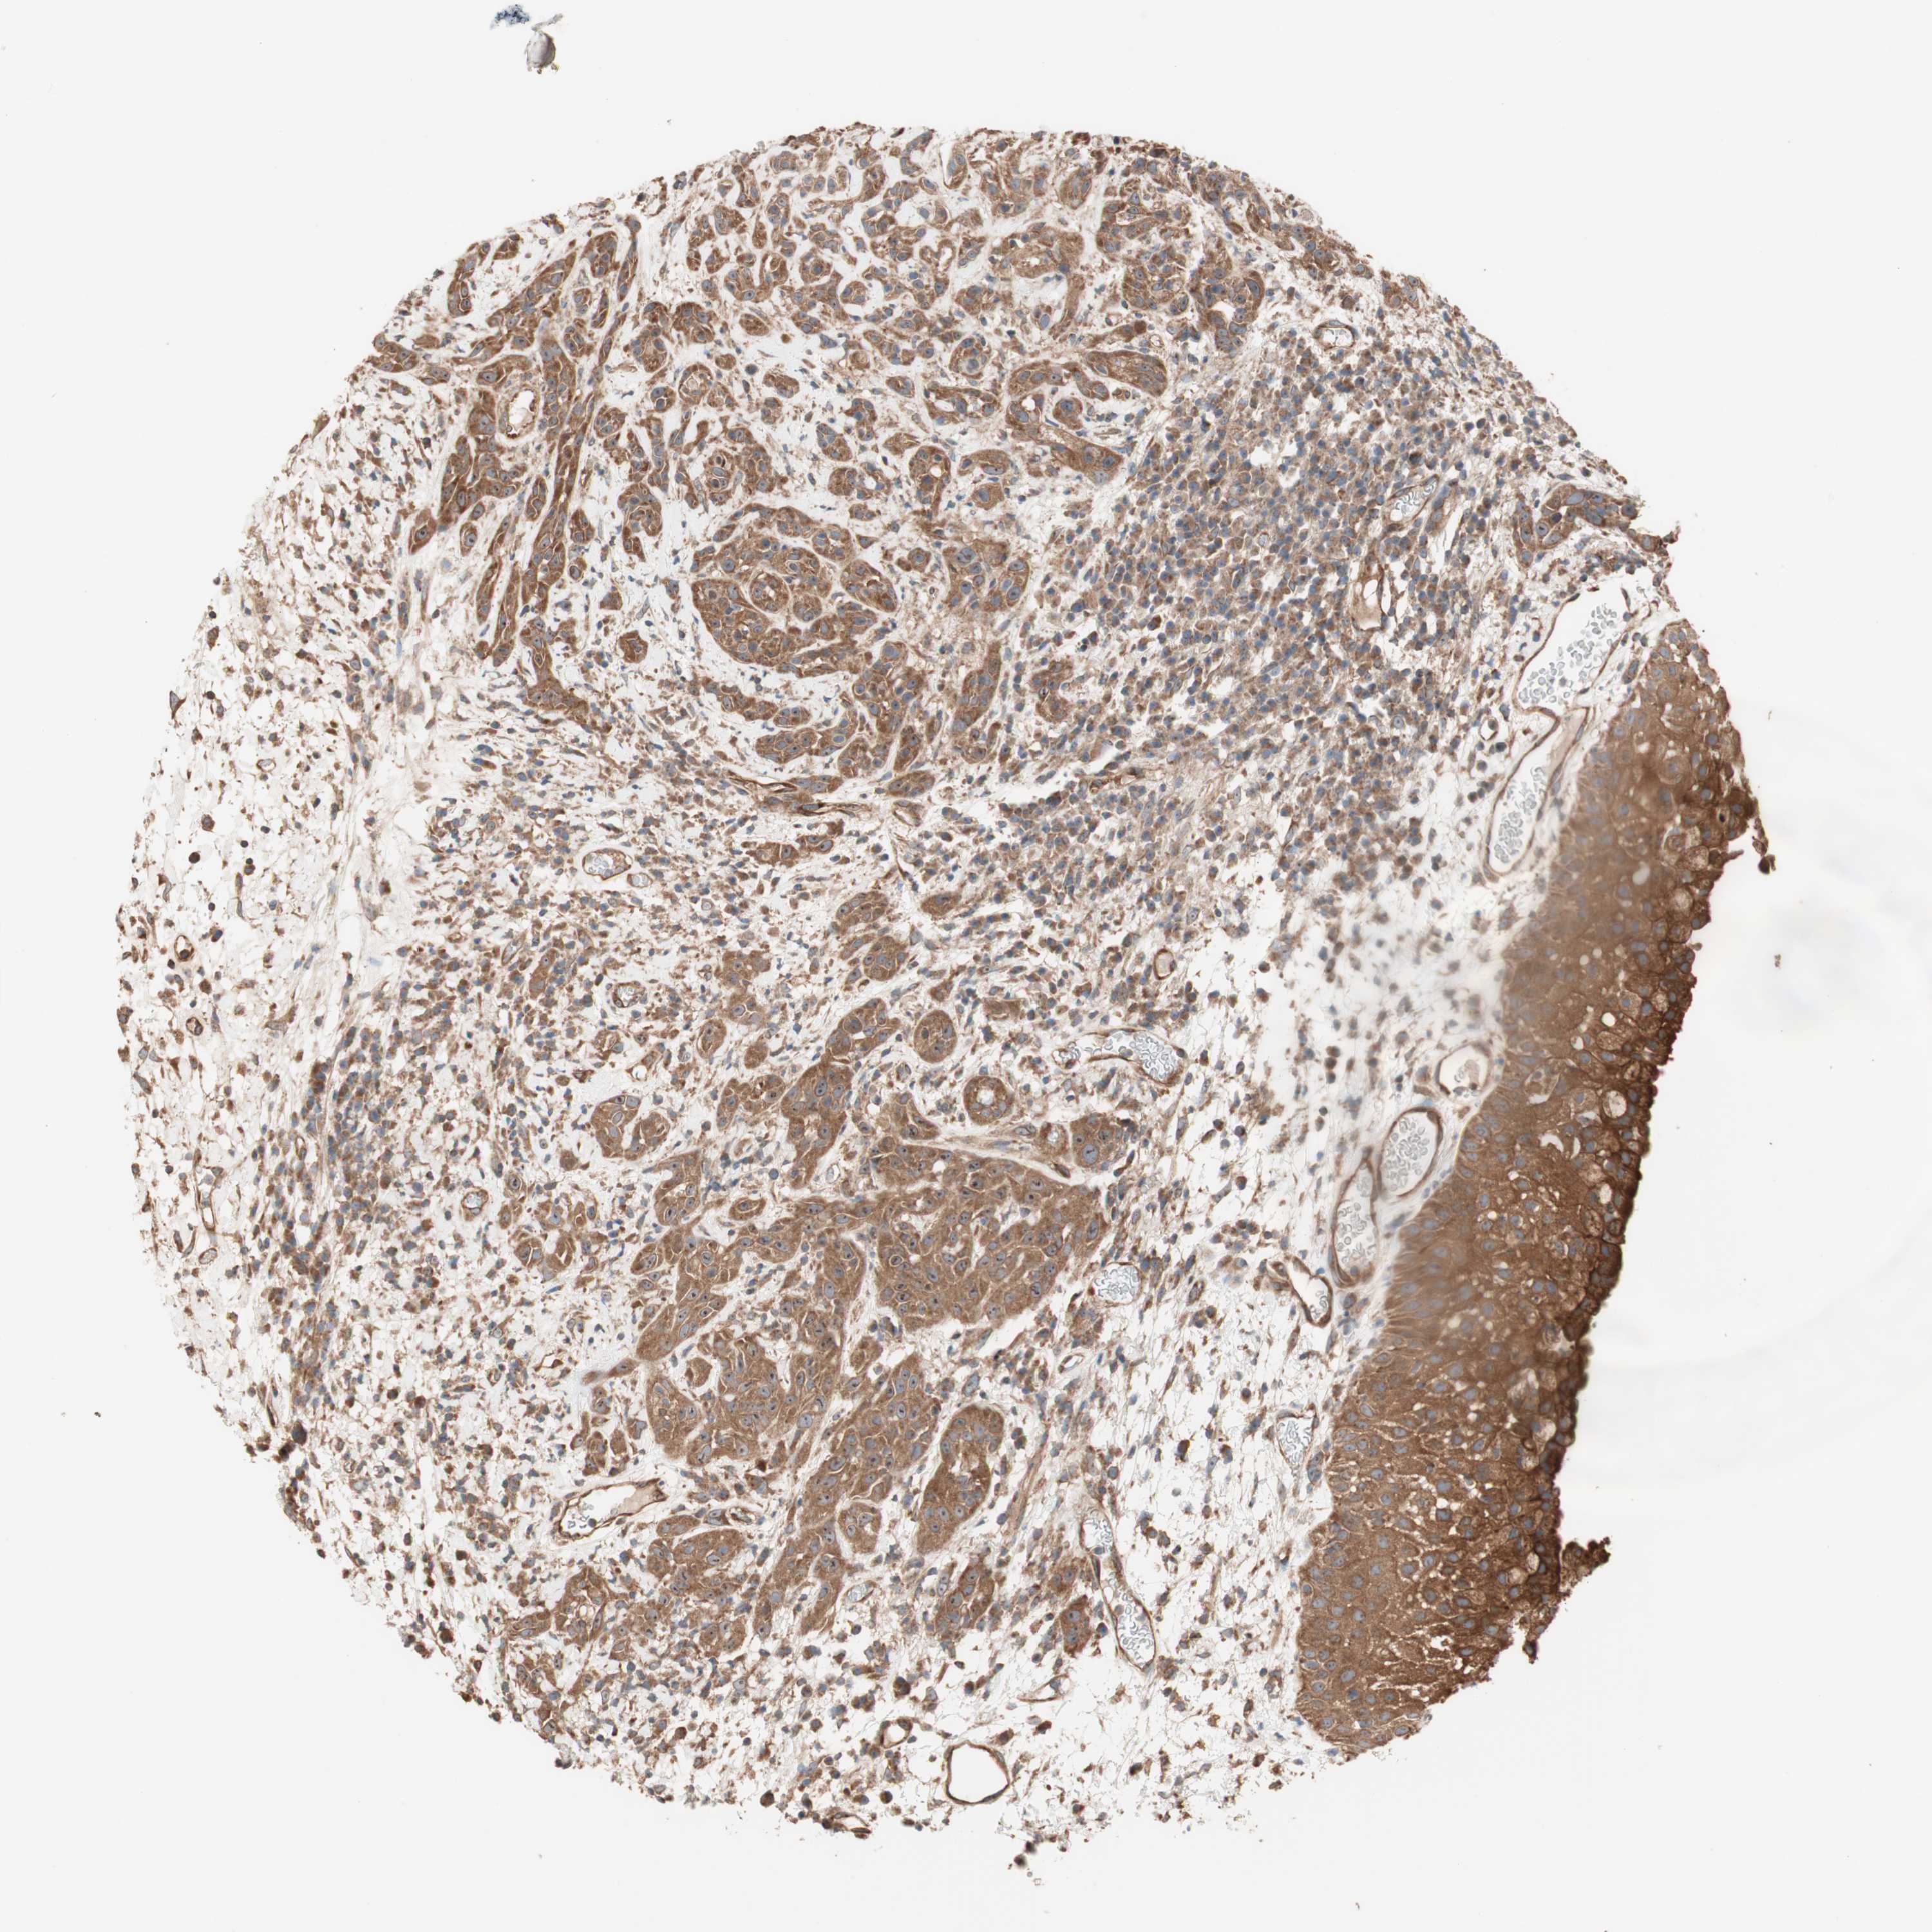

HEAD AND NECK CANCER - Protein expressioni

A mouse-over function shows sample information and annotation data. Click on an image to view it in a full screen mode. Samples can be filtered based on level of antibody staining by selecting one or several of the following categories: high, medium, low and not detected. The assay and annotation is described here.

Antibody stainingi

Antibody staining in the annotated cell types in the current human tissue is reported as not detected, low, medium, or high, based on conventional immunohistochemistry profiling in selected tissues. This score is based on the combination of the staining intensity and fraction of stained cells.

Each image is clickable and will lead to virtual microscopy that enables deeper exploration of all samples and also displays staining intensity scores, fraction scores and subcellular localization as well as patient and tissue information for each sample.

Antibody HPA007301

Staining

High

Medium

Low

Not detected

Intensity

Strong

Moderate

Weak

Negative

Quantity

>75%

75%-25%

<25%

None

Location

Nuclear

Cytoplasmic/membranous

Cytoplasmic/membranous,nuclear

Squamous cell carcinoma, NOS